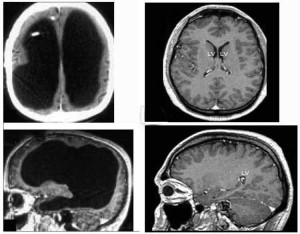

So the doctors did a CAT scan and an MRI. The results were astounding. Some tiny chambers that usually hold cushioning cerebrospinal fluid had enlarged. See this photo:

The black spaces on the left are filled with fluid.

The photos on the right show a normal brain for comparison.

He was essential missing most of his brain. Although he wasn’t a genius by any standard, he was living a successful and happy life. How could this be? Unless…